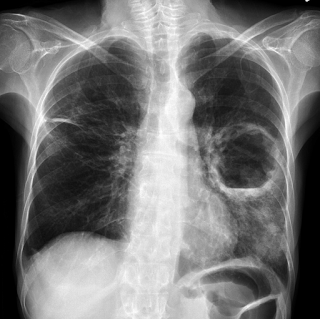

Work-related lung disease among coal miners, also known as black lung disease, results from breathing in coal mine dust, which causes inflammation and scarring, or fibrosis, in the lungs. Coal mine dust can also cause chronic obstructive pulmonary disease, or COPD. Regular screening is critical to catch early stages of black lung disease so that steps can be taken to prevent progression to severe disease. In the United States, coal miners are entitled to receive free screening when they start working in the industry and about every 5 years after that for as long as they keep working in coal mining. NIOSH recommends that miners take advantage of this important opportunity.

To understand this increase, NIOSH investigators analyzed data from the Coal Workers’ Health Surveillance Program. The NIOSH program provides the opportunity for all current coal miners to receive confidential health screenings at no cost to the miner. The investigators identified 192 miners who developed severe lung disease after the year 2000 and who had received at least two chest radiographs. It was found that most of these miners had a normal initial radiograph before progressing to severe lung disease nearly 21 years later, on average. Although almost half of the miners progressed from normal to severe lung disease in more than 20 years, 16.6% progressed in less than 10 years, and 35% in 11–20 years. Participants’ average age at the beginning of the study was 29 years, and all were male. Most worked in Kentucky, Virginia, or West Virginia.